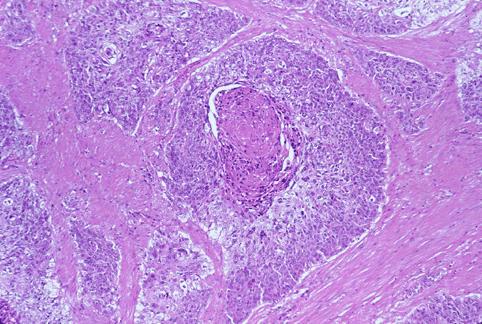

直腸下部の扁平上皮癌の病理組織像  癌組織は固有筋層を浸潤し、高分化扁平上皮癌の像を呈しています。一部に、癌真珠といわれる角化を伴っています。

疾患(病理主体)の分類悪性上皮性腫瘍/腺扁平上皮癌

部位(臓器別)大腸/直腸

検査方法ミクロ

腫瘍の深達度ss(a1)